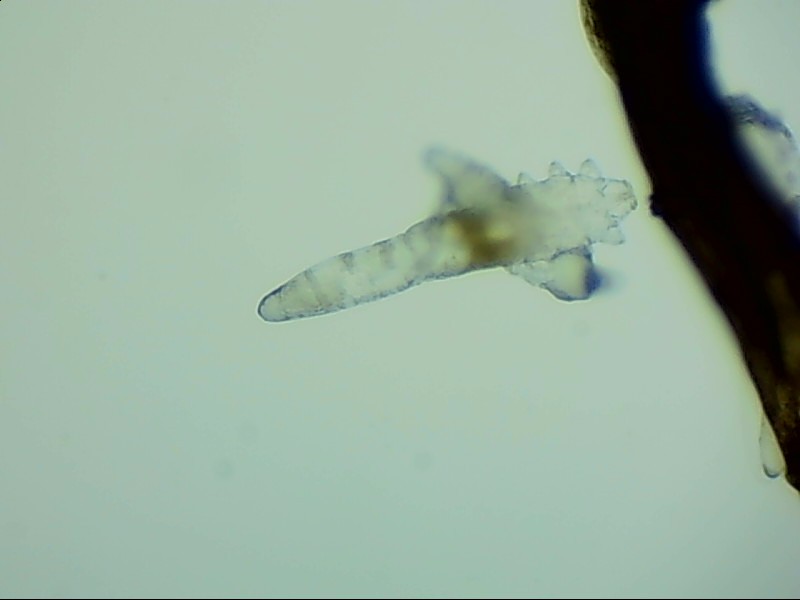

蠕形螨完全長大也只有0.1-0.2毫米,因此肉眼難以看到它們,只有在電子顯微鏡下我們才能看到睫毛根部的一只只蠕形螨。這些螨蟲每天都很活躍,且繁殖速度極快,完成一代生活史僅需大概15天。

螨蟲無所遁形,螨蟲鏡檢:

螨蟲鏡檢主要是通過顯微鏡觀察,它能無死角放大你的睫毛,讓螨蟲無處可躲。

在檢查的時候,醫(yī)生要在每個眼瞼上拔出幾根比較典型的睫毛,然后放在光學(xué)顯微鏡下,尋找有沒有螨蟲,同時觀察螨蟲的數(shù)量多少。

如果任意一個眼瞼上螨蟲數(shù)量較多,再加上你的眼睛有局部癥狀,后續(xù)就需要進(jìn)行相應(yīng)的治療了。